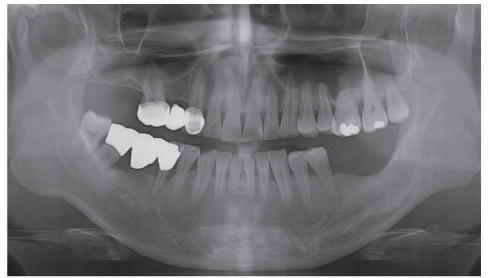

Figure 2

Preoperative panorama view. Periapical radiolucency was observed at the apex of mandibular left second premolar.

Figure 2 Preoperative panorama view. Periapical radiolucency was observed at the apex of mandibular left second premolar.